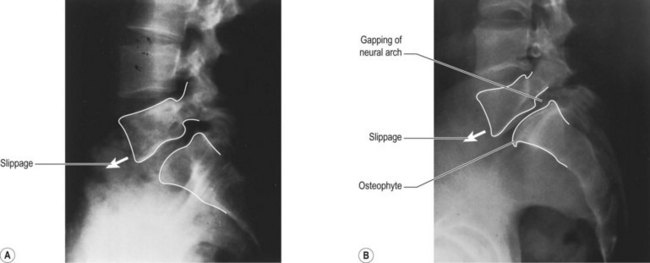

Spondylolysis 277

Spondylolisthesis 279

Management of spondylogenic disorders 279